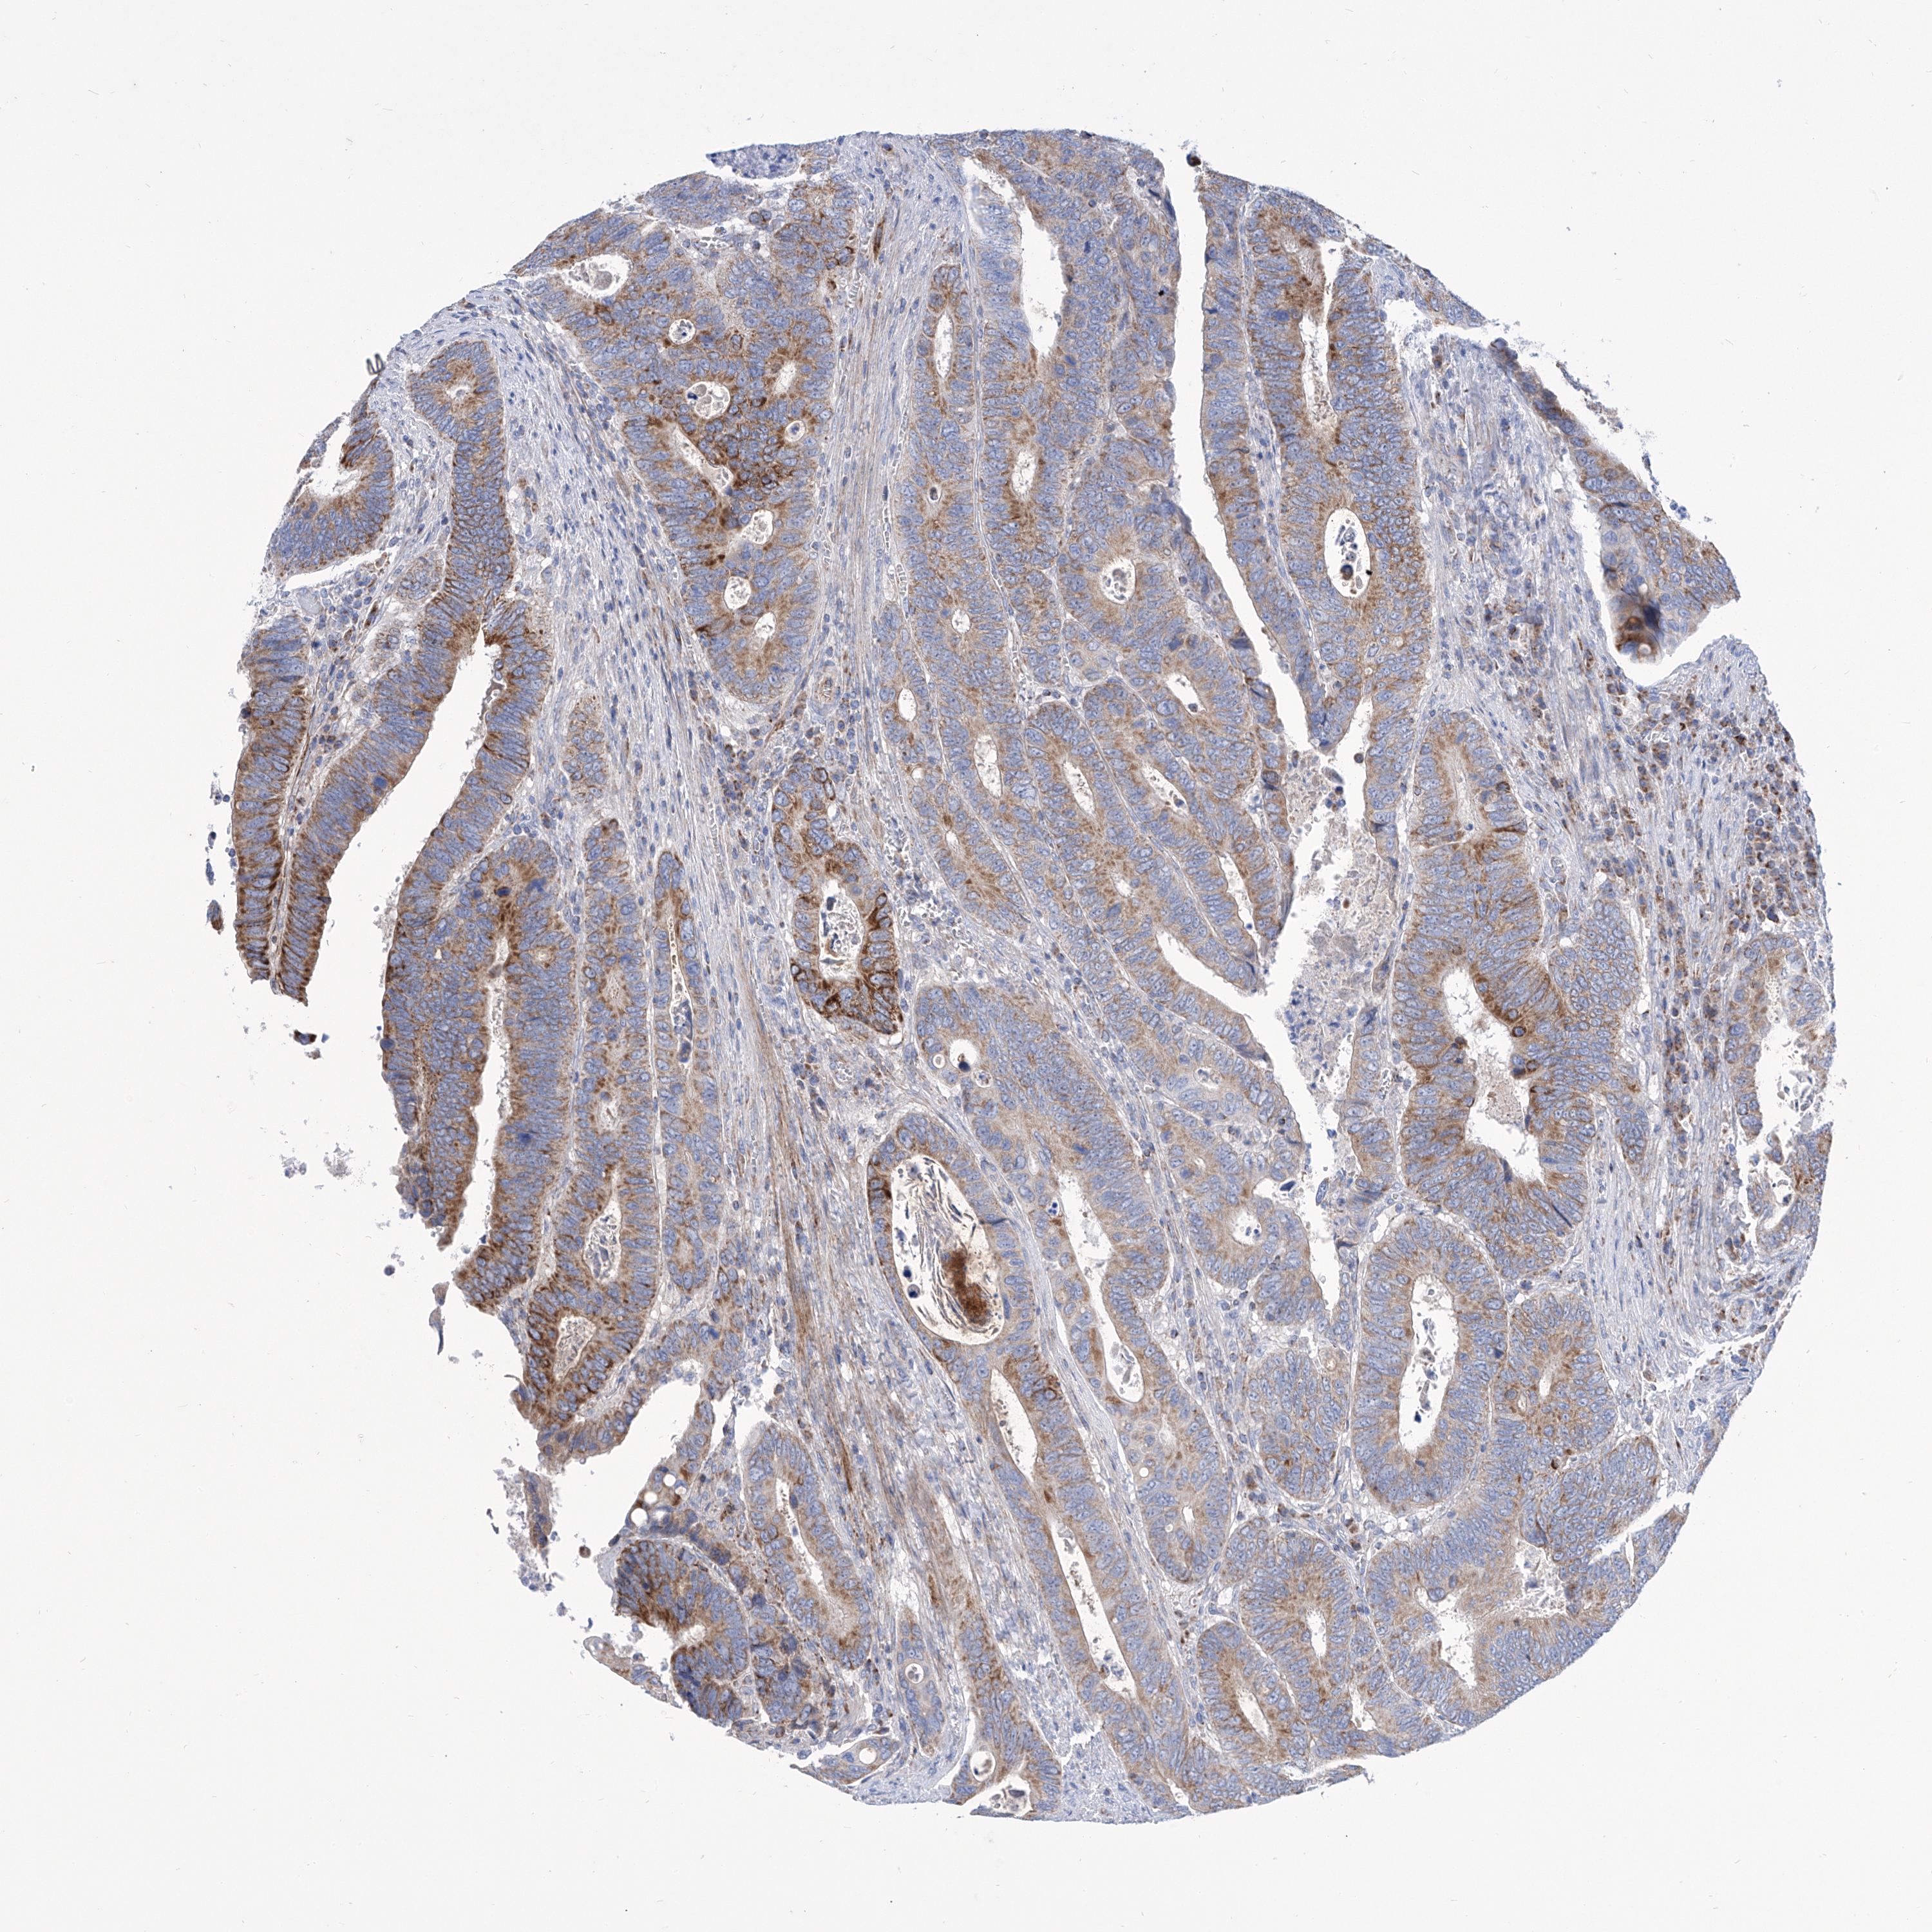

CANCER COLORECTAL CANCER Show tissue menu

Colorectal cancer

Human cancer

Colon adenocarcinoma

Rectum adenocarcinoma